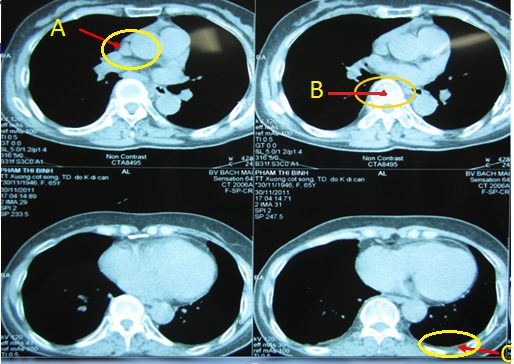

Sau đó chúng tôi tiếp tục ứng dụng một số kỹ thuật chẩn đoán khác để đi tìm ổ ung thư nguyên phát. Cụ thể là: Bệnh nhân được chụp CT 64 dãy lồng ngực cho kết quả là hình ảnh tổn thương đốt sống D7 và xâm lấn phần mềm cạnh cột sống bênh phải, theo dõi tổn thương ác tính, có vài hạch nhỏ trung thất, ít dịch màng phổi hai bên.

(Trên hình ảnh CT 64 dãy lồng ngực:(A): Hạch trung thất; (B): Tổn thương đốt sống D7 xâm lấn xung quanh; (C): Dịch màng phổi trái)